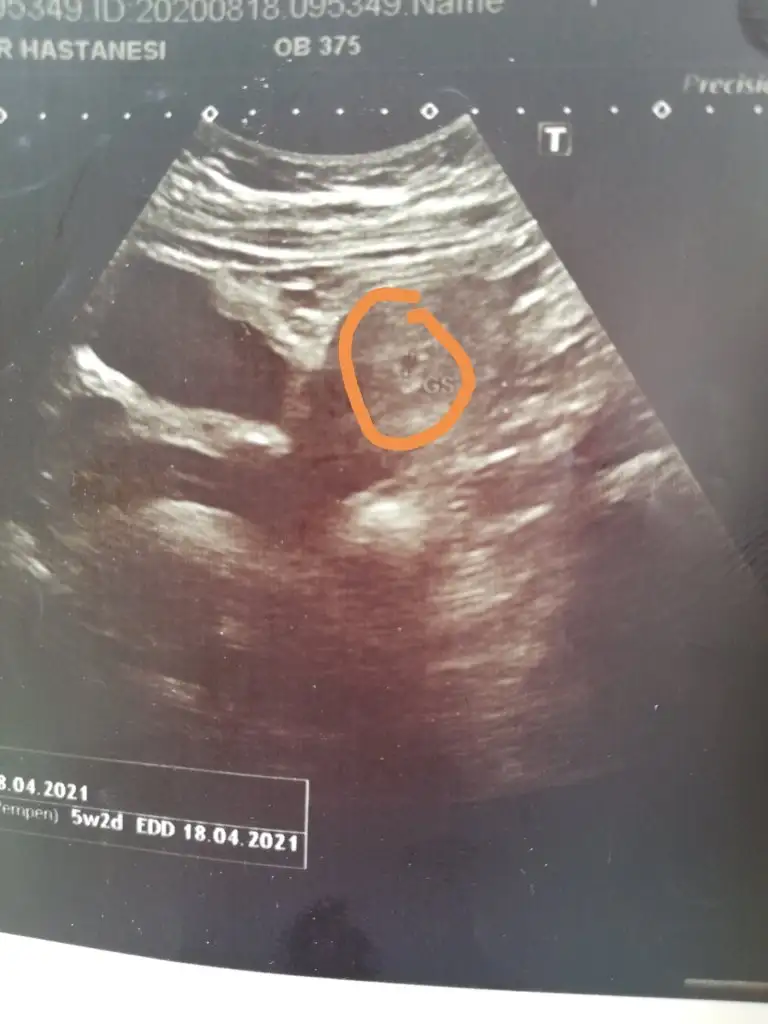

Kızlar ben de doktora gittim bugün sat tarihime göre 6+1 ama ultrasonla göre 5+2 karından çekildi. Biliyorum çok erken ama var mı bir tahmin. Bu arada sanırım işaretledipim yer kese olsa gerek

Eklentiler

• IMG_20200818_151149.webp

IMG_20200818_151149.webp

24,3 KB · Görüntüleme: 69

Burada biraz daha net sanki kızlar. Ramzi teorisi keseye göre mi kesenin içindeki bebişe göre mi yorumlanıyor